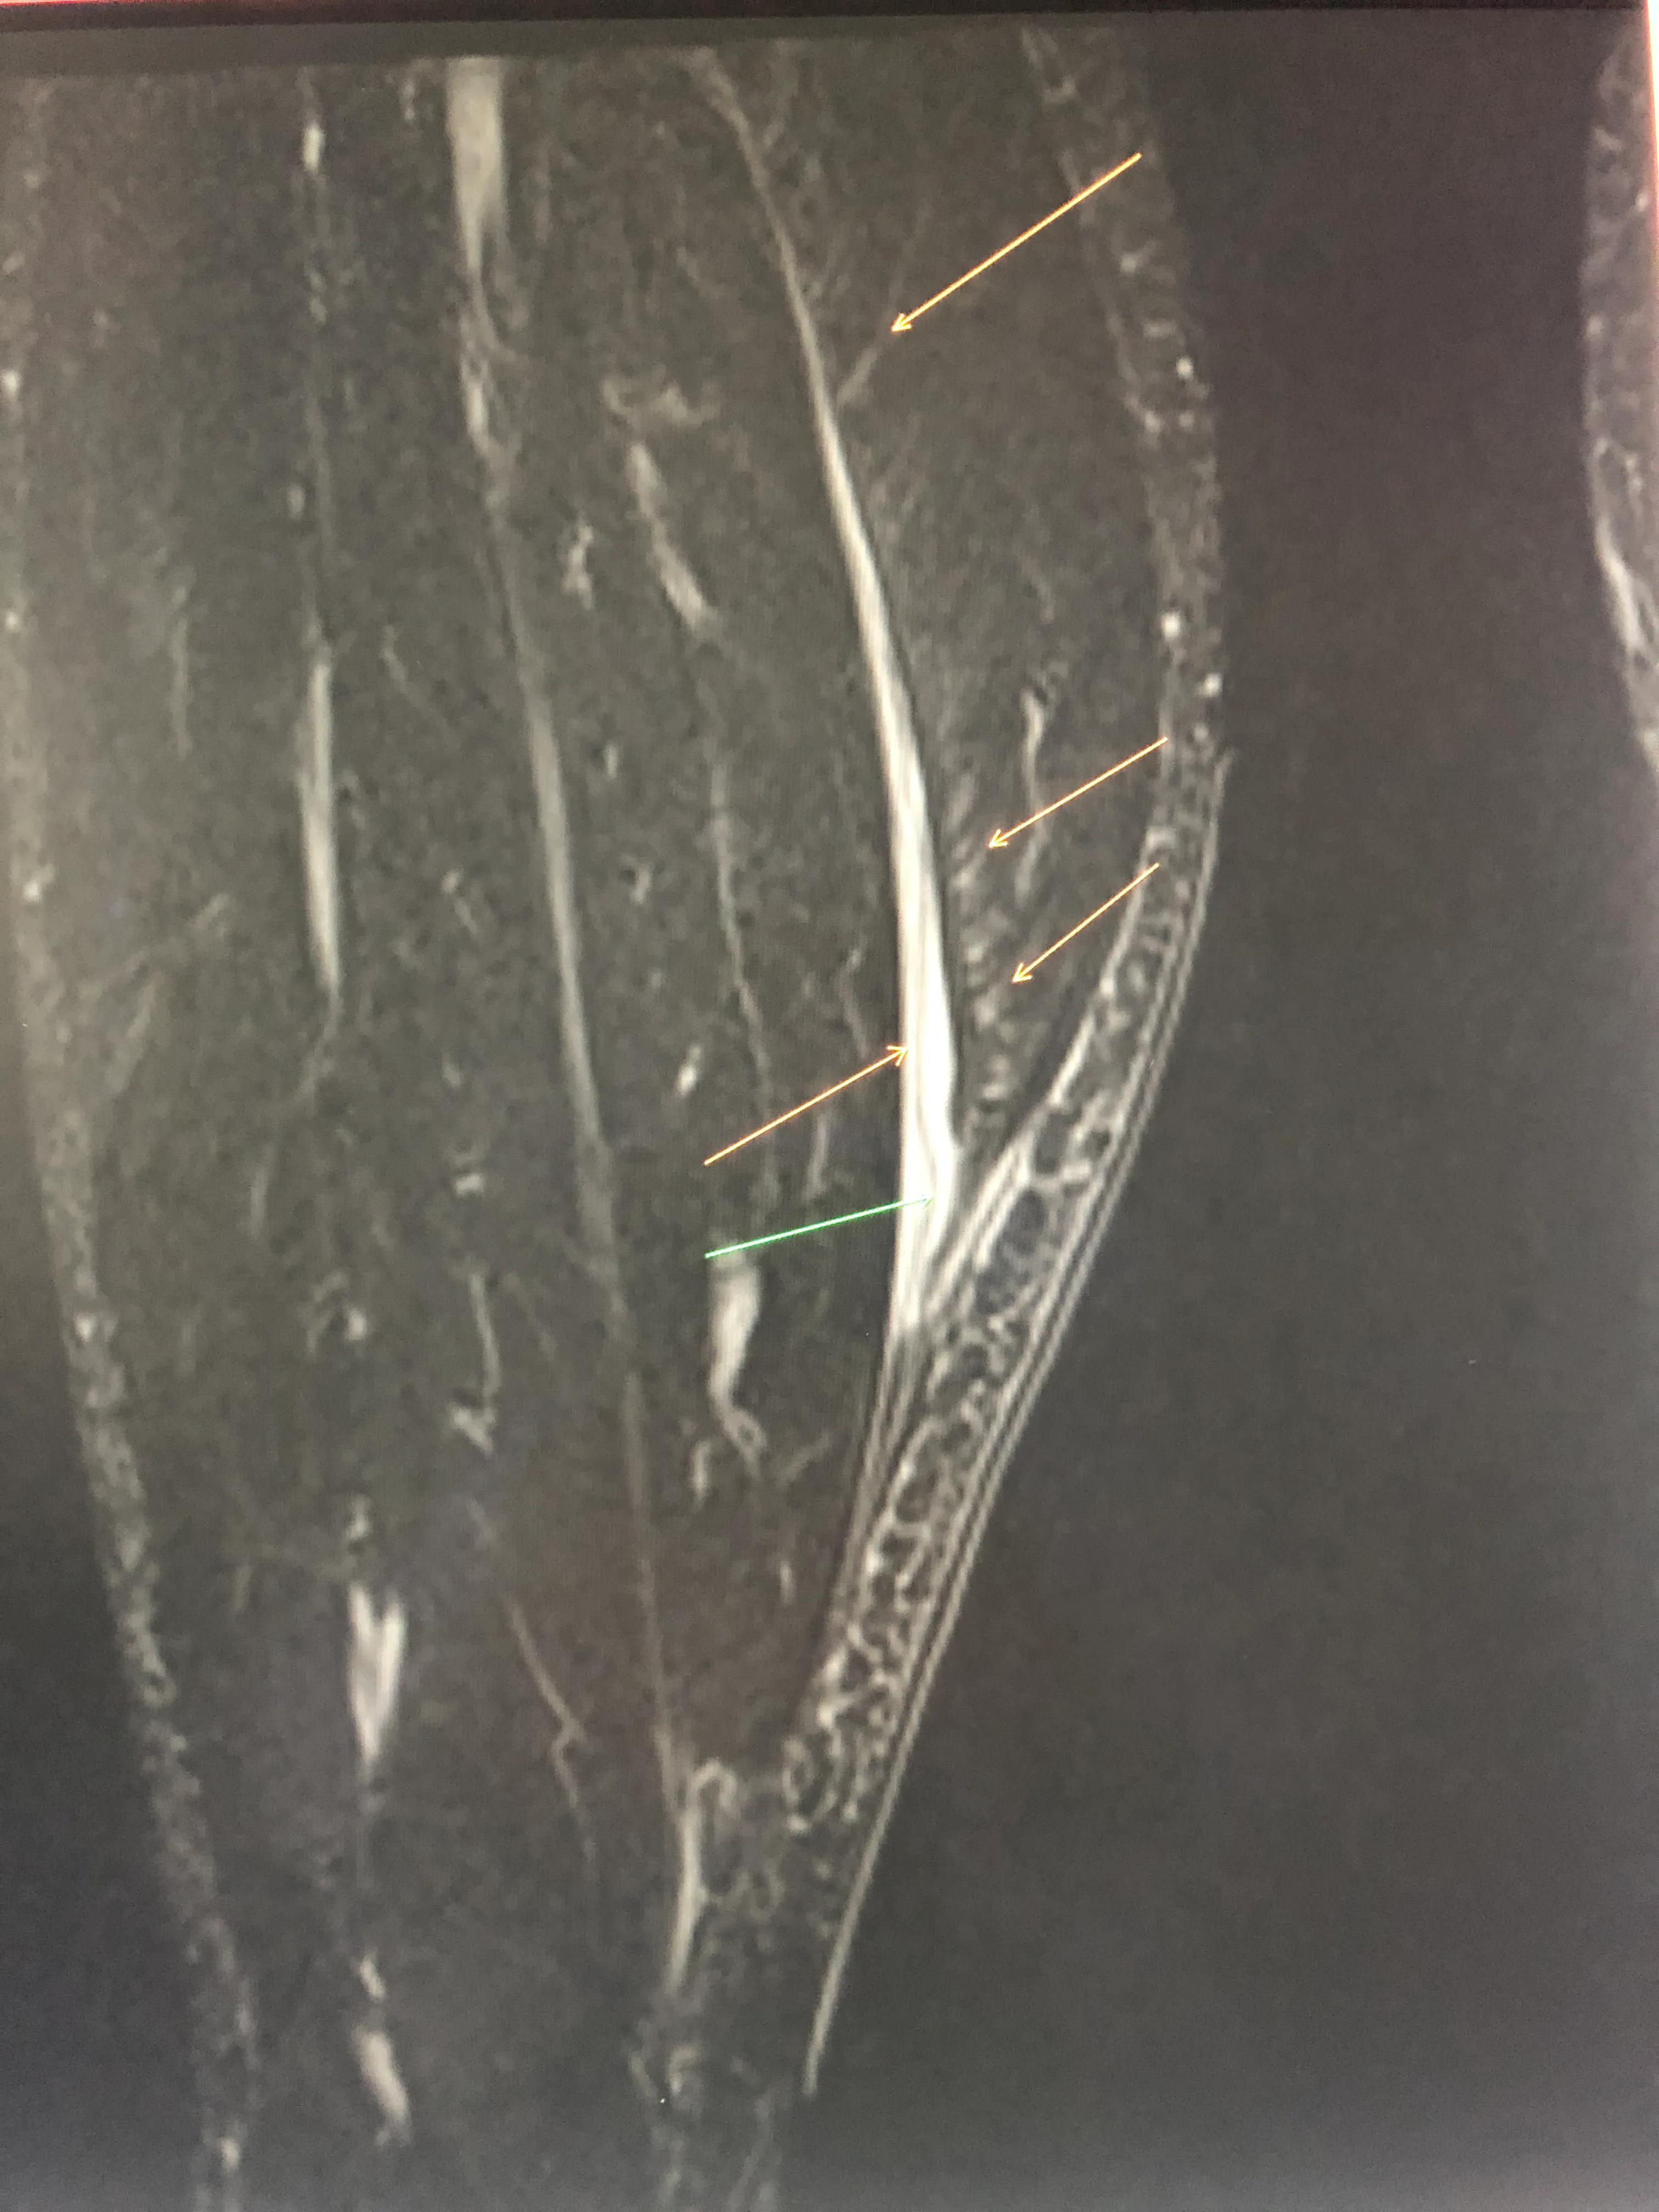

图1: MRI图像,经过技术处理后,图片中白色的都是渗血。黄色箭头表示的是撕裂的腓肠肌,绿色箭头标示的是肌腱部分撕裂。